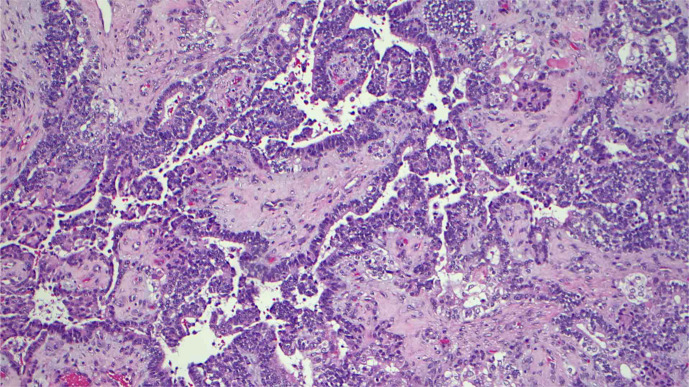

Case presentation: We report a case of a 48-year-old female patient who presented with headache, nausea, and vomiting. Initial imaging revealed a 6.4 × 4.5 cm extra-axial mass in the right frontal region, originating from the superior right nasal cavity. She underwent surgical resection of the tumor and was found to have SNTCS. She received concurrent chemoradiotherapy. Next-generation sequencing showed mutations in the PTEN, SMARCA4, and CCND1 genes. Six months after completion of treatment, she experienced an aggressive leptomeningeal recurrence of her disease. To our knowledge, our case represents the first SNTCS case with a documented PTEN mutation. In the absence of evidence-based guidelines due to the rarity of this diagnosis, we have reviewed over 50 cases reported in the literature.